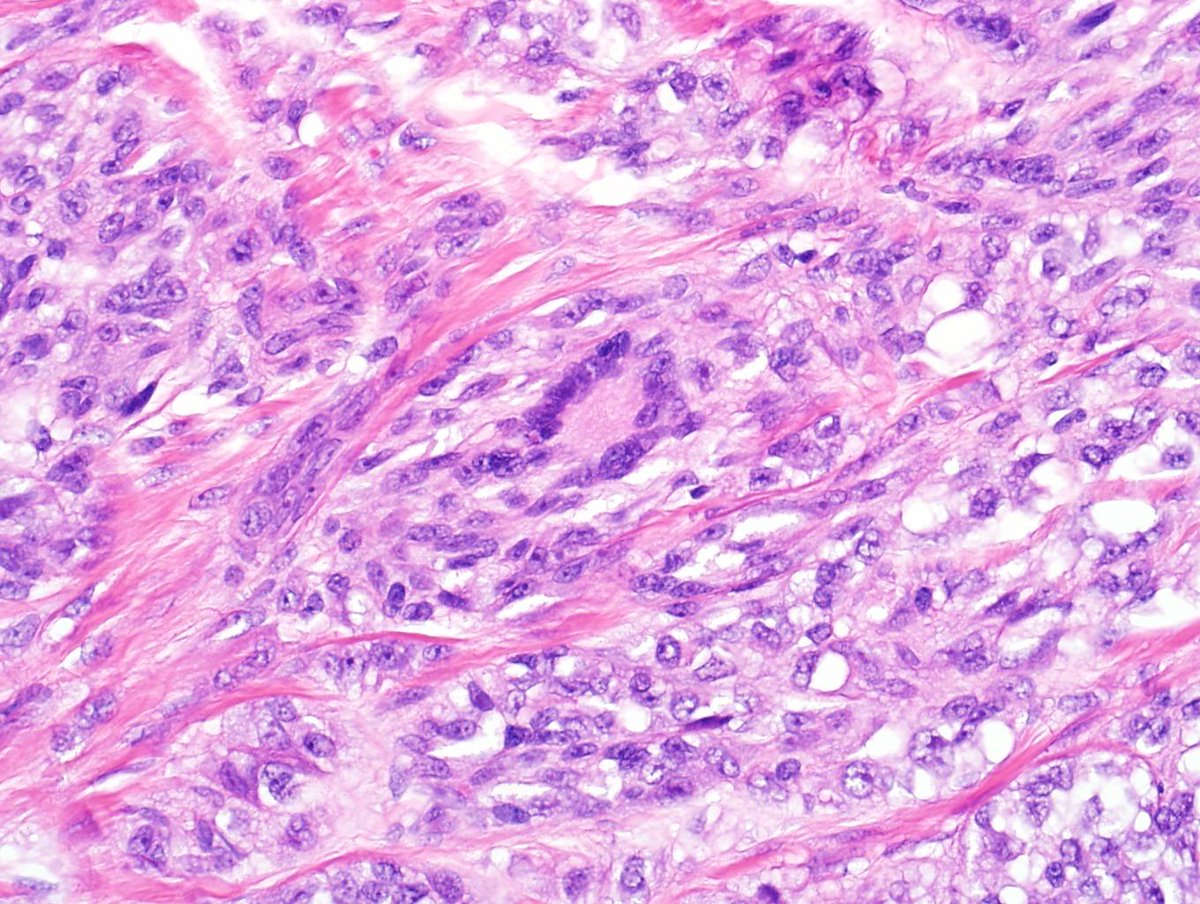

Thank Ash and Gary for hosting the IAC webinar. Allison and Carmen kindly helped the recording. I'm really thankful for over 200 online participants for those two talks. Grateful for the opportunity of doing contribution.